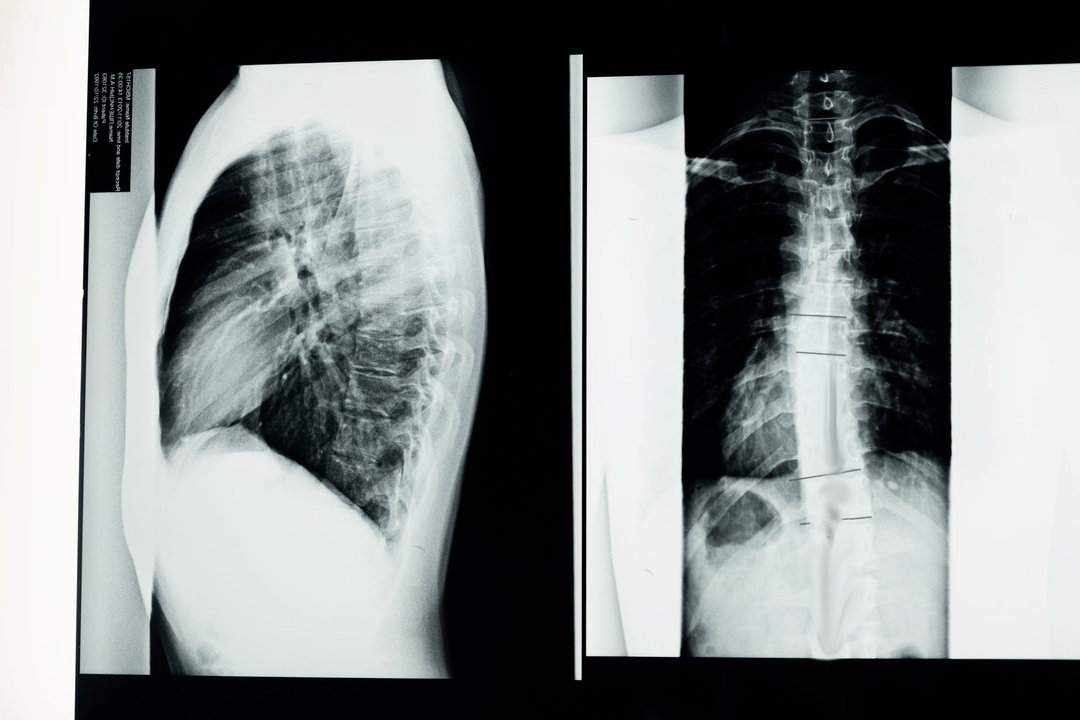

Tanı çalışmalarına başlamadan önce nörolog, hastanın tıbbi geçmişini alır ve şikayetlerini dikkatle inceler. Osteokondrozun diğer bazı hastalıklarla ortak semptomları vardır, bu nedenle patolojileri ayırt edebilmek önemlidir. X-ışını çalışmaları osteokondroz tanısını doğrulamaya yardımcı olacaktır: radyografi, miyelografi ve bilgisayarlı tomografi.

Anket röntgeni, omurganın veya bir bölümünün röntgen görüntüsünü elde etmenizi sağlar. Bu sayede doktor hastalığın etkilediği yeri tespit edebilir. Açıklık sağlamak için, osteokondrozun röntgen ile nasıl belirlenebileceğini açıklayacağız: görüntü, omurlararası diskin daralmasını, kemik büyümelerinin (osteofitlerin) varlığını veya omurga segmentinin şeklindeki bir değişikliği gösterecektir.